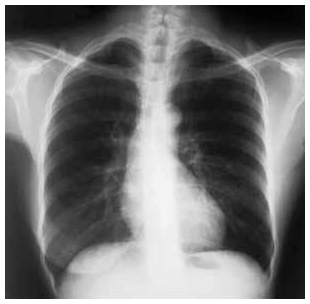

Uma mulher com 68 anos de idade foi atendida no ambulatório de um posto de saúde, com relato de tosse produtiva com

expectoração mucoide, que vem ocorrendo há mais de três anos. Informou ser tabagista (45 maços/ano) e que, nos últimos seis meses,

passou a ter dispneia progressiva aos esforços físicos. O exame físico mostrou: paciente dispneica leve, acianótica, pressão arterial de

120 mmHg × 80 mmHg, frequência cardíaca de 80 bpm, frequência respiratória de 22 irpm, com ritmo cardíaco regular em 2 tempos,

bulhas cardíacas hipofonéticas e ausência de sopros à ausculta cardíaca, diâmetro anteroposterior da caixa torácica aumentado, presença

de hipersonoridade à percussão do tórax e murmúrio vesicular reduzido de forma difusa, com roncos esparsos à ausculta pulmonar; o

restante do exame não apresentou anormalidades. Abaixo é reproduzida a radiografia do tórax em projeção posteroanterior realizada para

essa paciente.

Tendo por base as informações clínicas e a radiografia de tórax apresentadas, julgue os itens a seguir.

Aumento dos espaços intercostais e da translucidez pulmonar, retificação das cúpulas diafragmáticas, dilatação do tronco da artéria pulmonar e cardiomegalia moderada (especialmente à custa do átrio direito) são anormalidades que podem ser vistas no radiograma torácico mostrado.Uma mulher com 68 anos de idade foi atendida no ambulatório de um posto de saúde, com relato de tosse produtiva com